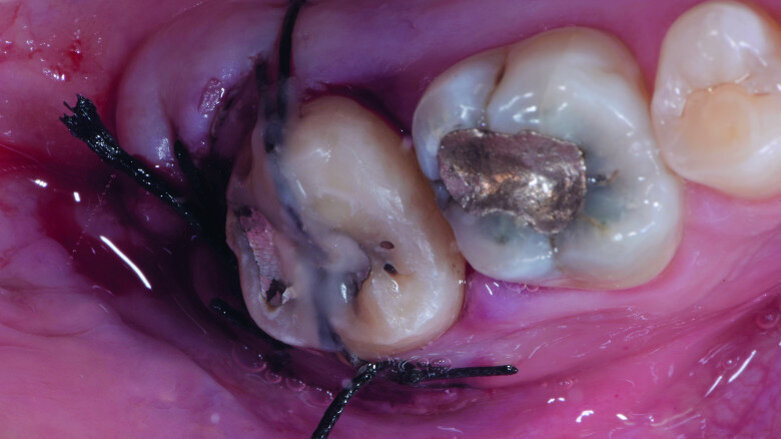

Fig. 12: Pulp chamber floor perforation, immediately after extraction.

Fig. 13: Pulp chamber floor perforation, tooth cleaned.

After local anaesthesia with 2 per cent mepivacaine with 1:100,000 adrenaline, the right maxillary second molar was atraumatically extracted. Initially with a size 15c surgical blade, the periotomy was realised and then the tooth was extracted after separating the roots to avoid unnecessary trauma to the alveolar bone. Then the donor right maxillary third molar was extracted after periotomy as described and transplanted into the adjacent site. Because of the slight differences in the root anatomy, it was necessary to remove the intraradicular bone septum of the receiving site to al- low tooth positioning, and a odontoplastic of the donor tooth crown was performed to maintain it not in occlusion. An antibiotic (amoxicillin/clavulanic acid, 1 g, by mouth twice a day for five days) was prescribed, along with rinses with 0.2 per cent chlorhexidine. The tooth was keep stable with sutures (Fig. 8). A periapical radiograph was taken (Fig. 9). At the suture removal at two weeks, the tooth showed good stability, and positive adaptation of the soft tissue was observed (Fig. 10). At four weeks, the tooth was stable and the soft tissue looked healthy (Fig. 11). The patient did not show any adverse effects and stated that the tooth was fully functional. Examination of the avulsed second molar showed the extent of the perforation (Figs. 12 & 13).